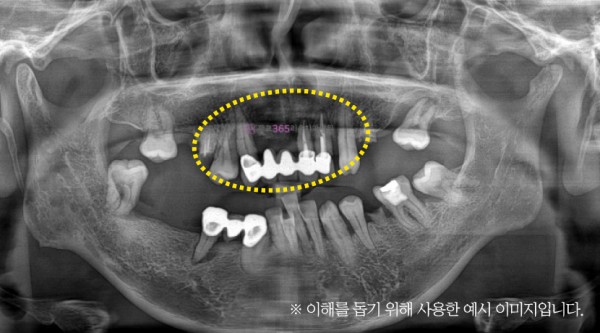

뼈이식 해야될까? | 뼈이식은 꼭 해야하는 건가요?